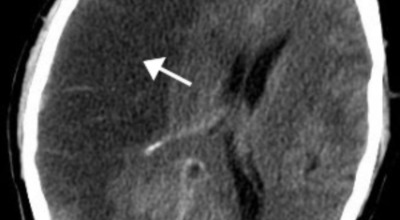

뇌졸중 뇌출혈 차이점

뇌졸중 - 뇌에 혈액을 공급하는 혈관이 막히거나 터져 뇌 손상을 일으키는 상태

뇌출혈 - 뇌혈관이 파열되어 출혈이 발생하는 상태

뇌경색 - 뇌혈관이 막혀 혈액 순환이 원활하지 않은 상태

뇌졸중 치료는 약물, 재활, 그리고 수술로 이루어집니다. 뇌졸중은 단 몇 분만 혈액 공급이 끊겨도 뇌세포가 손상되는데, 뇌세포는 한 번 죽으면 되살릴 수 없기 때문에 가능한 한 빨리 환자를 병원으로 데려가 원인을 파악하고 치료하는 것이 매우 중요합니다. 뇌경색(뇌졸중) 진단을 받으면 3시간 이내에 병원에 도착해 혈전용해 치료를 받게 됩니다.

이 치료법은 약물을 사용해 혈전을 녹이는 방식으로, 장시간 사용하면 안전하지 않기 때문에 환자가 추가 합병증을 일으키거나 경색이 재발하는 것을 막기 위해 제한적으로 적용됩니다. 만약 환자에게 출혈이 발생하면 외과적 치료가 필요할 수 있습니다.